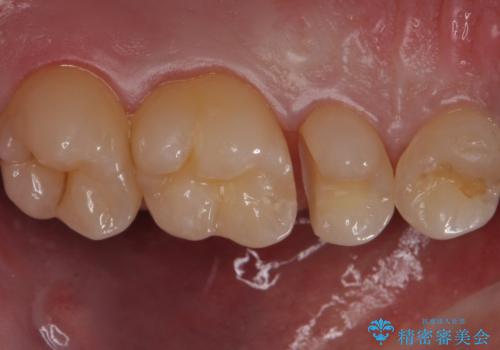

歯と歯の間の虫歯 セラミックインレーでの治療

- 検査の結果虫歯が見つかった患者様です。

レントゲン画像と視診から詰め物で対応可能と判断したためインレーでの修復をしていきます。

適合の良いインレーは段差がない上にセラミックは汚れがつきにくい材料であるため今後の虫歯発生リスクを抑えることに繋がります。